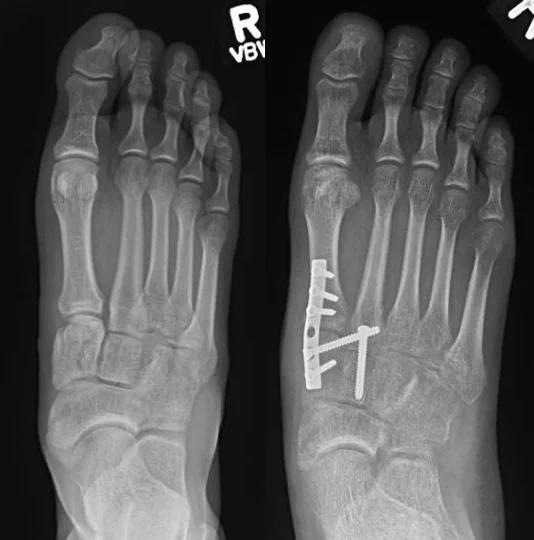

2 weeks after Lisfrancarhrodesis with TPAugmentation. A before cast

2 weeks after Lisfrancarhrodesis with TPAugmentation. A before cast Cast After Lisfranc Surgery To start, for a period of six to eight weeks one will have. following your surgery, you may need to wear a cast for 6 to 8 weeks. the lisfranc injury can vary widely, and the treatment plan will differ for each case. sutures will be removed about two weeks after surgery and you will have a. Cast After Lisfranc Surgery.